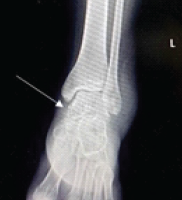

A 64-year-old female presented following a mechanical fall at work, reporting bilateral hip pain, more pronounced on the left side. The patient had no history of hip pain before the fall. Clinical examination demonstrated a preserved range of motion in both hips, with discomfort on weight bearing but no focal neurological deficit. Initial anteroposterior pelvic radiography demonstrated no acute fracture, but revealed a well-defined lucent lesion in the proximal left femur (Fig. 1). A computed tomography (CT) scan of the pelvis was subsequently performed to exclude an occult fracture. CT confirmed an elongated intramedullary lucent lesion within the proximal left femoral metaphysis, characterized by sclerotic margins without cortical destruction, endosteal scalloping, or an associated soft-tissue mass, suggesting a non-aggressive process (Fig. 2 and 3).

Figure 2: Axial computed tomography image at the level of the proximal femur showing a centrally located intramedullary lucent lesion with preserved cortical integrity and absence of endosteal scalloping or periosteal reaction (arrow).

Figure 3: Coronal computed tomography of the pelvis demonstrating an elongated, well-defined intramedullary lucent lesion within the proximal left femoral metaphysis (arrow), with sclerotic margins and no cortical destruction or soft-tissue extension, consistent with a non-aggressive lesion.